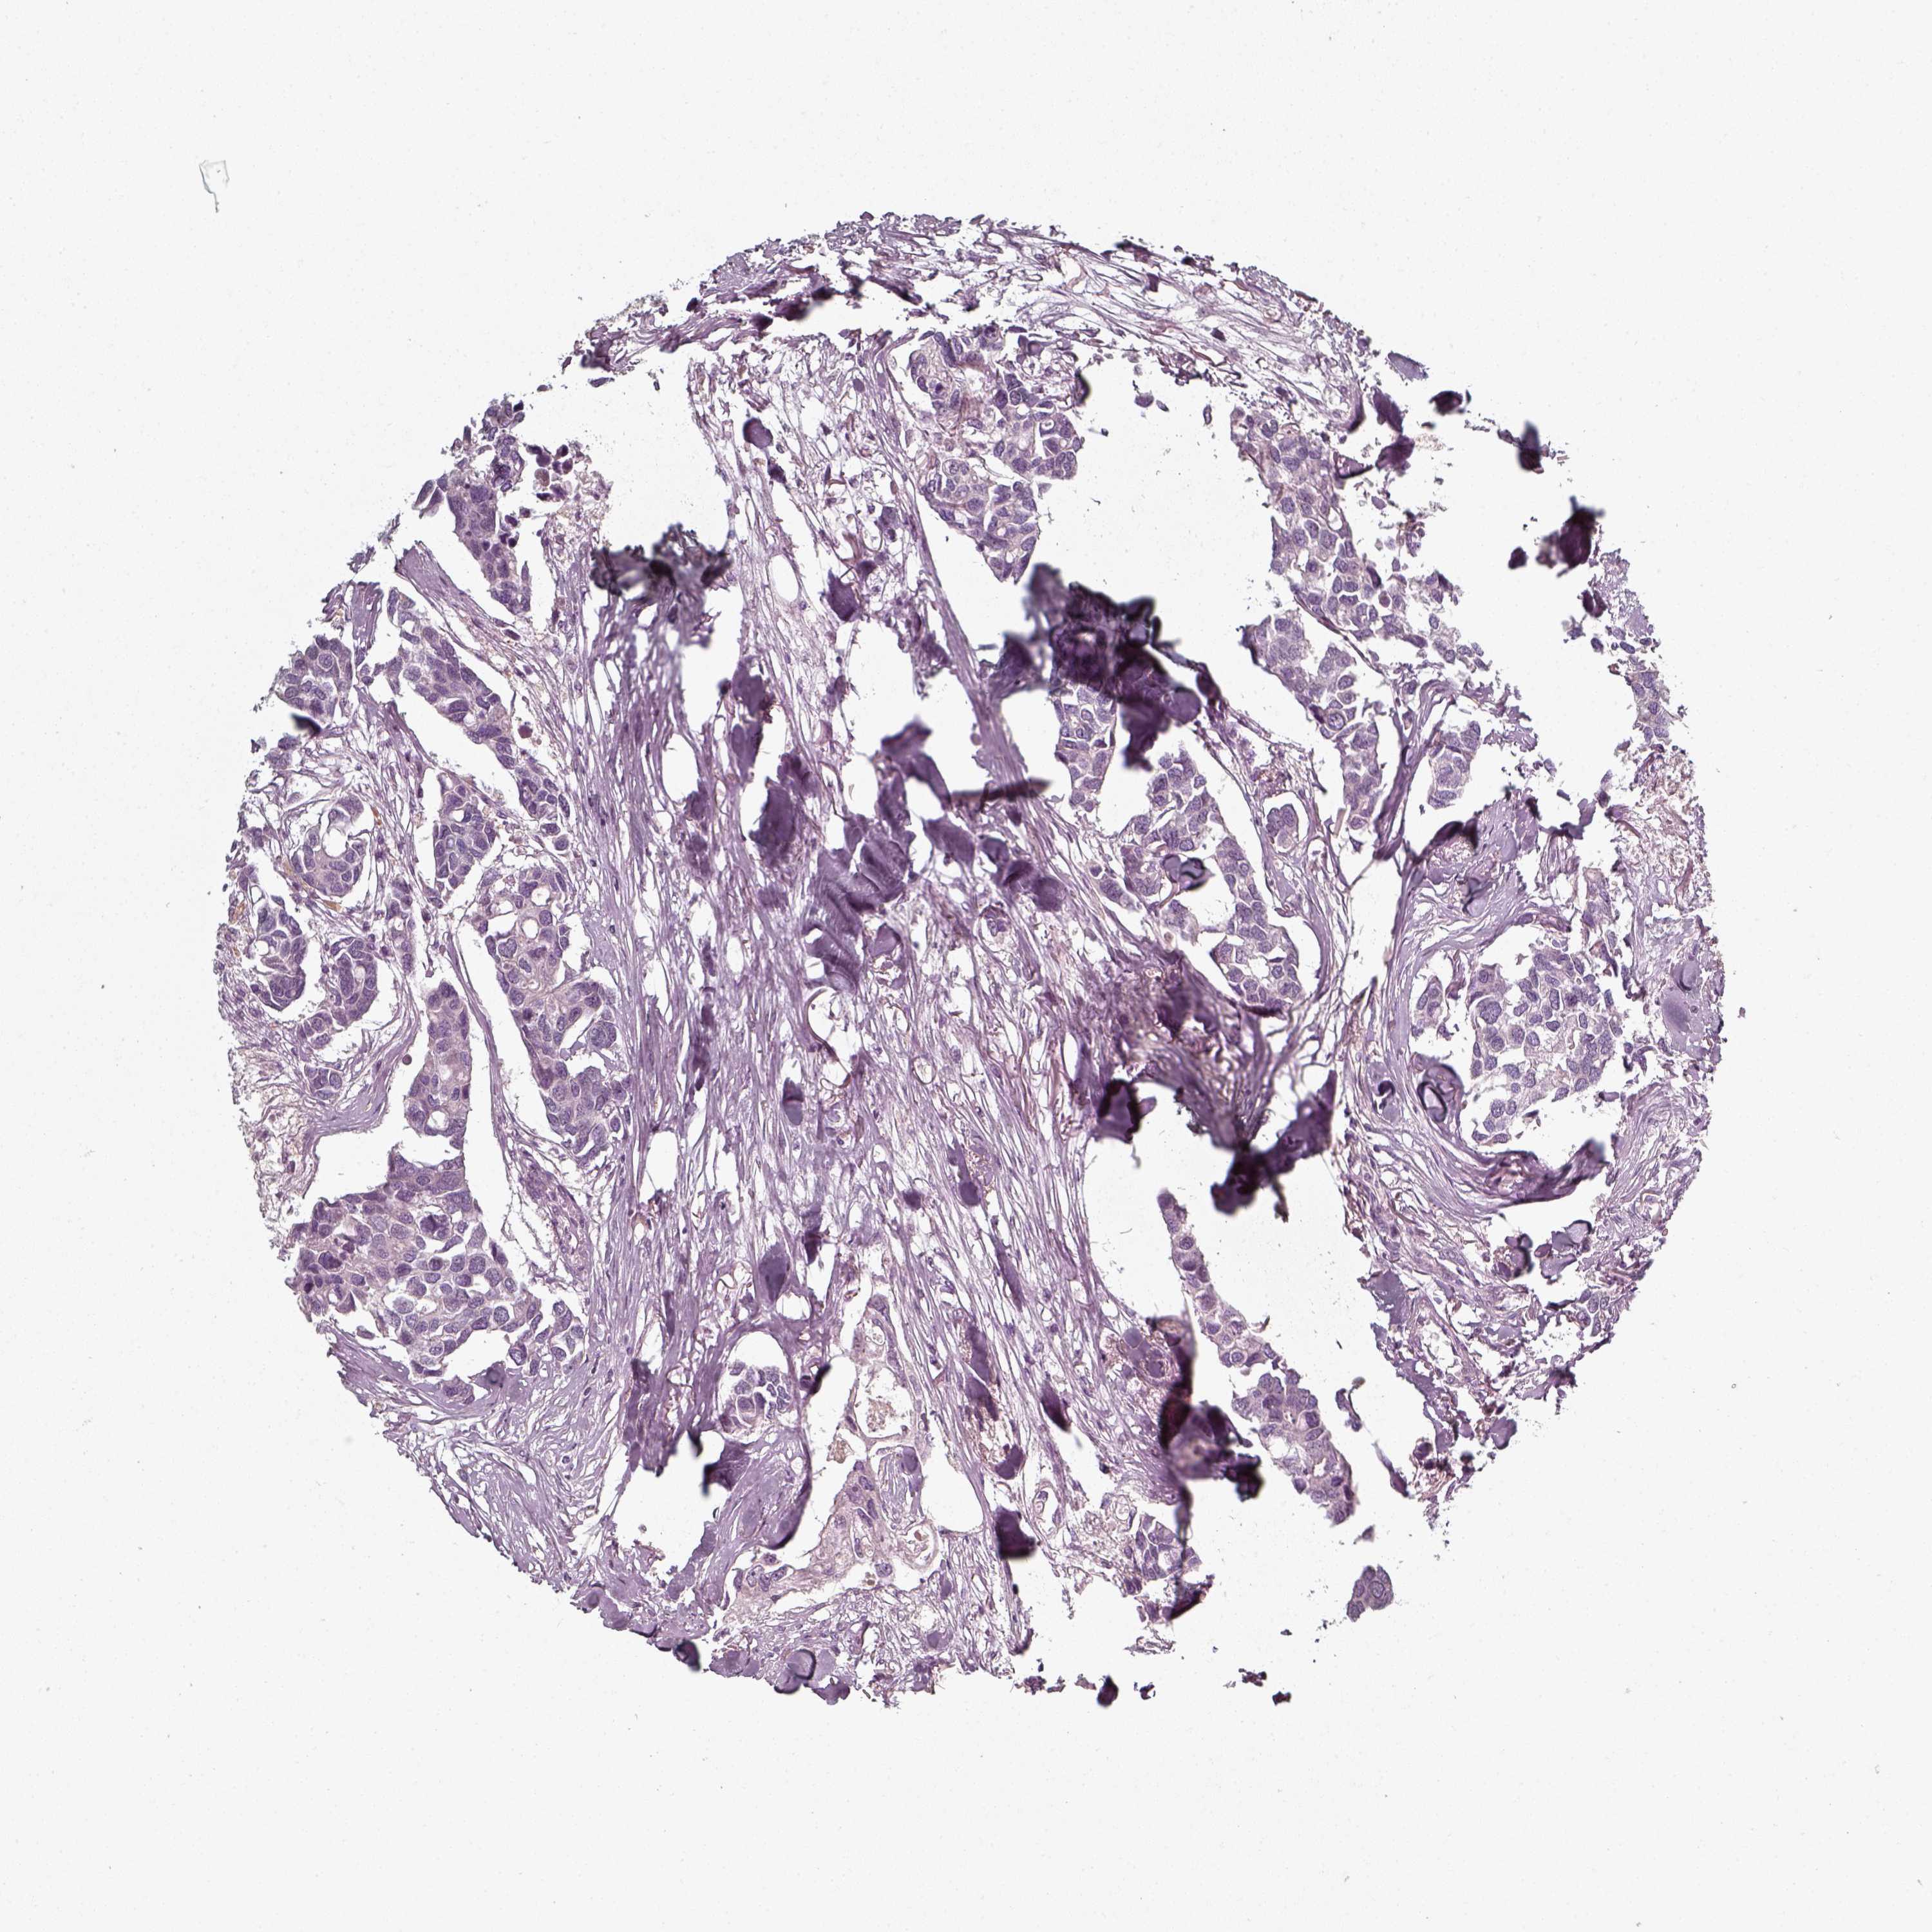

CANCER BREAST CANCER Show tissue menu

BRCA TCGA BRCA VALIDATION PROTEIN EXPRESSION